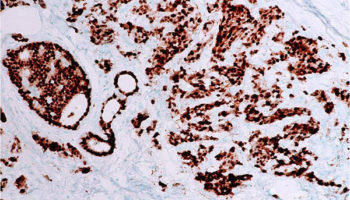

An immunostain that marks a gene that is involved in cell proliferation or growth. The degree of Ki67 labeling in a cancer cell correlates to how quickly the tumor is growing and how aggressive it is. The measure ranges from 0% (no cells dividing) to 100% (all cells dividing). See also proliferation index.

A type of laboratory test that can detect the proteins expressed by a cell. The test uses special antibodies (“immunostains”) that each binds to a particular protein in question; the immunostain will change the color of the tissue to show whether a protein is present. Examples include immunohistochemistry to look for HER-2 overexpression, as well as the expression of the estrogen receptor (ER) and progesterone receptor (PR) in breast cancer cells.

A measure of how rapidly a tumor is growing by assessing how many cells are dividing. The measure ranges from 0% (no cells dividing) to 100% (all cells dividing). (See also Ki67.)